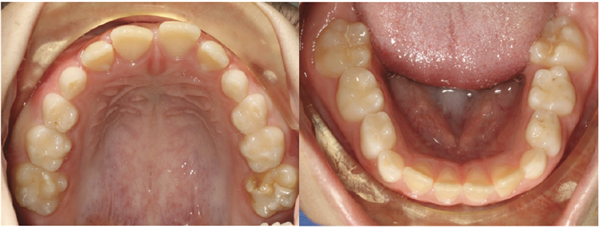

The Brodie bite was fully corrected. The lower left posterior segment was successfully uprighted and buccally positioned, establishing functional intercuspation on the left side for the first time. Upper anterior spaces were consolidated through the anterior U2–2 segment. The lower midline was shifted to the left and now aligns with the upper midline. The asymmetry of the patient’s chin was also corrected, which further aided in midline alignment. Arch form and coordination were significantly improved in both arches, with the mandibular arch demonstrating meaningful expansion compared to baseline (Figs. 6–7).

Fig. 7: Final intraoral and occlusal photographs demonstrating correction of the Brodie bite, improved arch coordination, elimination of upper spacing, and improved midline alignment.